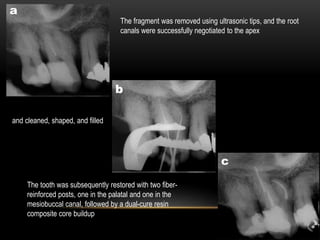

The fragment was removed using ultrasonic tips, and the root

canals were successfully negotiated to the apex

and cleaned, shaped, and filled

The tooth was subsequently restored with two fiber-

reinforced posts, one in the palatal and one in the

mesiobuccal canal, followed by a dual-cure resin

composite core buildup